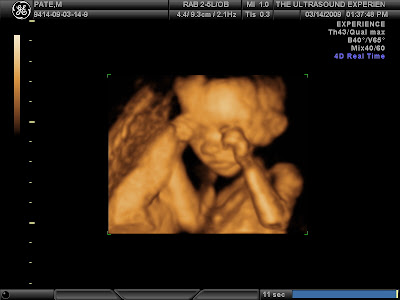

Although Megan was VERY sick for a large portion of the pregnancy thus far, things have been much better lately and there is something really cool that we did last weekend that I now would recommend to anyone – The 3D ultrasound experience which is actually what the place is called. We invited the family to come and watch because we knew we’d be told what we are having. Our tech was really nice and it was a really comfortable experience. Right away she was able to tell the results…It’s a GIRL! We are so stoked.